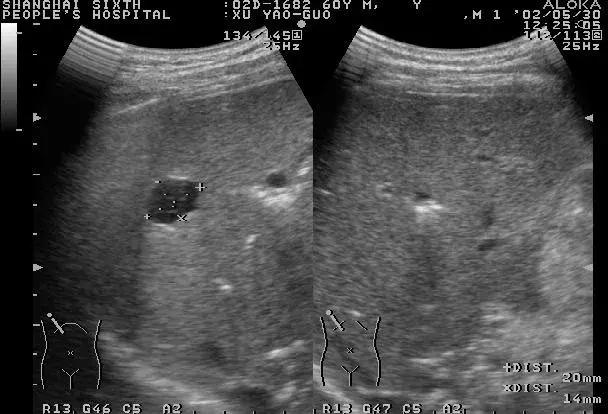

超声检查是肝脏影像学检查首选的方法,具有价廉、便捷、无创等优点。常规超声能显示肝脏大小形态,肝内实质结构、管道系统、血管走向与分布,明确有无肝脏结节、具体的大小与部位、初步鉴别结节的良恶性,适用于常规体检和结节的定期复查。

值得一说的是,随着超声技术的发展,彩色多普勒超声可以诊断直径小于1cm的病变,在有经验的单位,准确率可达90%以上。

对于B超不能明确诊断的,建议做增强CT扫描或MRI检查,对于高度怀疑肝细胞癌的可行“肝动脉造影”检查。

各种影像学检查不但可以配合定性论断,还可以进行定位论断,也就是进一步确定肝脏结节在肝脏上的位置、大小、数目及其与周围组织的关系,为进一步治疗方案提供依据。